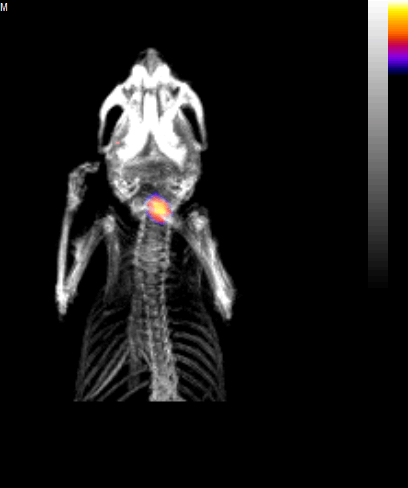

將小鼠左頸動脈血管暴露接觸氯化鐵,誘導(dǎo)血栓形成。隨后注射Targ-Cy7或Mut-Cy7熒光探針,45分鐘后在FLECT成像設(shè)備上掃描,可視化小鼠體內(nèi)的近紅外熒光三維分布。隨后立即進行X射線計算機斷層成像(CT),以確定小鼠的解剖結(jié)構(gòu),從而捕獲熒光信號的體內(nèi)精確定位。

結(jié)果表明,注射Targ-Cy7熒光探針后能夠清晰檢測到血栓(圖1B)。該信號定位于小鼠的左側(cè)頸動脈血管。

對血栓所在的感興趣區(qū)域的熒光強度進行定量,與Mut-cy7熒光探針在小鼠體內(nèi)的弱信號相比,Targ-Cy7熒光探針能夠顯著提高檢測到的信號強度(圖1C)。證明了FLECT成像設(shè)備檢測體內(nèi)血栓的能力。

作者隨后對頸動脈血管進行組織病理分析,以確認所有小鼠(Targ-Cy7和 Mut-Cy7)左側(cè)血管存在血栓,而右側(cè)血管健康無血栓(圖1D)。每條左頸動脈中檢測到的Targ-Cy7 FLECT信號與其血栓重量呈顯著正相關(guān)(圖1E,p =0.0006,r = 0.9807)。

圖1頸動脈血栓形成FLECT/CT成像閉塞性血栓形成FLECT/CT成像